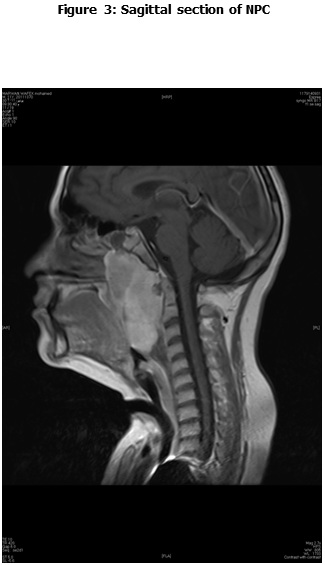

This is a retrospective study including all the newly diagnosed pediatric NPC who were diagnosed and treated at the Children Cancer Hospital Egypt (CCHE) during the period from July 2007 to December 2012. All imaging studies (e.g., CT or MRI scans) were reviewed by a senior head and neck radiologist for proper staging and assessment of tumor response. Patients were staged according to AJCC staging system. Modified version of the Response Evaluation Criteria in Solid Tumor (RECIST) was used to assess response.

This is a retrospective study including all newly diagnosed pediatric NPC at Children Cancer Hospital Egypt CCHE during the time period from July 2007 to December 2012. The patients' profiles were systematically reviewed for characteristics including pathology, laboratory, radiological work up and documented toxicities. All imaging studies (e.g., CT and MRI scans) were reviewed by a senior head and neck radiologist for proper staging and assessment of tumor response.

Pretreatment evaluation included a complete history and physical examination, complete blood count, serum biochemistry tests (including evaluation of electrolyte levels, hepatic and renal function tests), CT or MRI scans of the head and neck region, chest and bone scan. During therapy weekly examinations and laboratory evaluations were performed. Tumor response was assessed by clinical examination with appropriate MRI imaging studies after completion of neoadjuvant chemotherapy and at the end of radiotherapy.

Radiotherapy

Radiotherapy planning was performed 2-3 weeks after the third course of neoadjuvant chemotherapy. A customized thermoplastic immobilization cast was used for all patients and a CT simulation was applied using iv contrast injection and a 3 mm slice thickness. The gross tumor volumes (GTV) as well as all organs at risk were delineated. Clinical target volume was created by adding a safety margin that encompass all possible microscopic and expected tumor extensions. An isotropic expansion of 5 mm was added to form the planning target volume (PTV) according to the department policy. Intensity modulated radiotherapy (IMRT) technique using KonRad treatment planning system was applied to deliver a dose of 61.2 Gy in 37 fractions to high risk tumor and nodal areas, and 54 Gy to the low risk nodal area applying simultaneous integrated boost technique for CR and PR patients. Those who had SD received 66.6Gy in 37 fraction, while for patients with PD, they received 70.2 Gy in 39 fractions. Toxicity was recorded and graded according the WHO toxicity criteria.